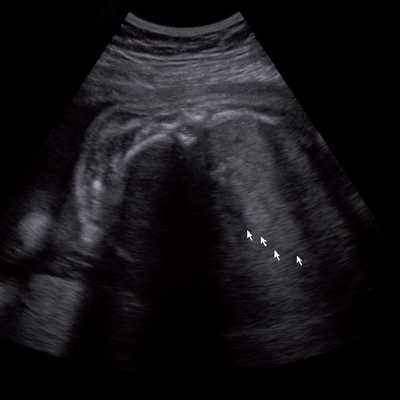

Под диафрагмой справа визуализировалось гиперэхогенное опухолевидное образование несколько неоднородной солидной структуры, с четкими ровными контурами, размером 50x38x35 мм. К нижнему полюсу данного образования прилежала правая почка, имеющая нормальные размеры, форму и структуру. Нижняя полая вена была смещена кпереди и влево. Обращала на себя внимание выраженная гепатомегалия, причем структура печени не была однородной. Она содержала множественные гиперэхогенные включения размерами до 17 мм, окруженные тонким гипоэхогенным периферическим ободком. Цветовое допплеровское картирование(ЦДК) демонстрировало интенсивную периферическую васкуляризацию опухоли (рис. 1-3).

Рис. 3. Метастазы в печени плода. Поперечное сечение брюшной полости плода. Гепатомегалия. В структуре печени плода определяются округлые включения несколько повышенной эхогенности (стрелки), с гипоэхогенным ободком - метастазы.